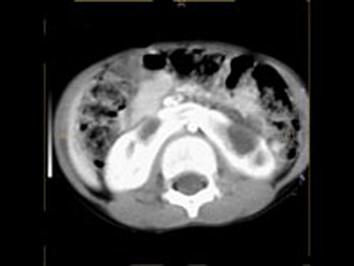

女,6个月,CT扫描如图所示,下列说法错误的是 ( )A、异位肾B、马蹄肾C、双侧肾门朝向前内方D、双肾下极融合E、双侧肾盂积水

问题 女,6个月,CT扫描如图所示,下列说法错误的是 ( )

选项 A、异位肾 B、马蹄肾 C、双侧肾门朝向前内方 D、双肾下极融合 E、双侧肾盂积水

答案 A